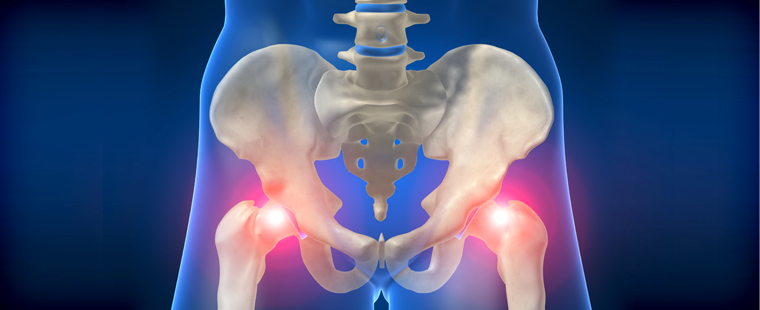

3. 고관절염

고관절염은 일차성(노화성)과 이차성(선천적 이상·외상·감염 등)으로 나뉩니다. 특히 국내에서는 이차성 고관절염 환자가 많은 편이며, 골반과 대퇴골의 구조적 손상을 초래합니다. 증상이 심해지면 걷는 동안 서혜부(샅)가 욱신거리거나 가만히 있어도 통증이 나타납니다.